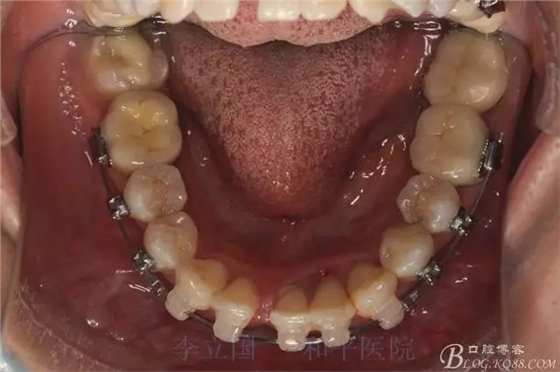

1.拔除14、24、31。

2.Damonclear排齊整平。

3.微種植支抗內(nèi)收上下前牙。

4.調(diào)整咬合關(guān)系。

2.磨牙關(guān)系一側(cè)完全遠(yuǎn)中,一側(cè)遠(yuǎn)中尖対尖,采用兩個(gè)上4,一個(gè)下1的拔牙模式。